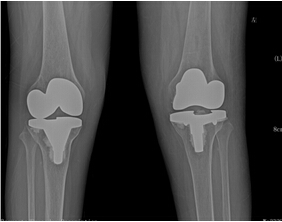

考慮到患者為長(zhǎng)期慢性病病人,唐雄主任決定先給患者疼痛程度更高的右側(cè)膝關(guān)節(jié)進(jìn)行手術(shù)治療。經(jīng)過完善備血、調(diào)整激素用量等術(shù)前準(zhǔn)備后,2015年10月10日,唐主任為患者進(jìn)行了右側(cè)膝關(guān)節(jié)人工關(guān)節(jié)置換術(shù),術(shù)后患者恢復(fù)良好。右側(cè)膝關(guān)節(jié)疼痛解除,術(shù)后3天右下肢能下地活動(dòng)。出院后,患者對(duì)右側(cè)膝關(guān)節(jié)置換術(shù)的效果非常滿意。 2016年7月17日,唐主任為該患者再次進(jìn)行了左膝關(guān)節(jié)人工關(guān)節(jié)置換術(shù)?;颊咝g(shù)后3天就能下地活動(dòng)。現(xiàn)在她的臉上又出現(xiàn)了燦爛的笑容,她逢人就說,要是早一點(diǎn)來手術(shù)治療,就能早一點(diǎn)擺脫病痛的折磨了。

人工髖、膝關(guān)節(jié)置換術(shù)是自上個(gè)世紀(jì)以來在醫(yī)學(xué)中最成功的手術(shù)之一,目前,對(duì)于各種終末期關(guān)節(jié)病治療,人工髖、膝關(guān)節(jié)置換術(shù)取得了革命性的成功。我院骨科二區(qū)關(guān)節(jié)外科自上世紀(jì)80年代開始就開展了人工關(guān)節(jié)置換術(shù),積累了豐富的經(jīng)驗(yàn)與技術(shù),此項(xiàng)手術(shù)技術(shù)成熟,病人愈后好,能徹底解決因長(zhǎng)期膝關(guān)節(jié)帶來的痛苦,大大提高了病人的生活質(zhì)量。